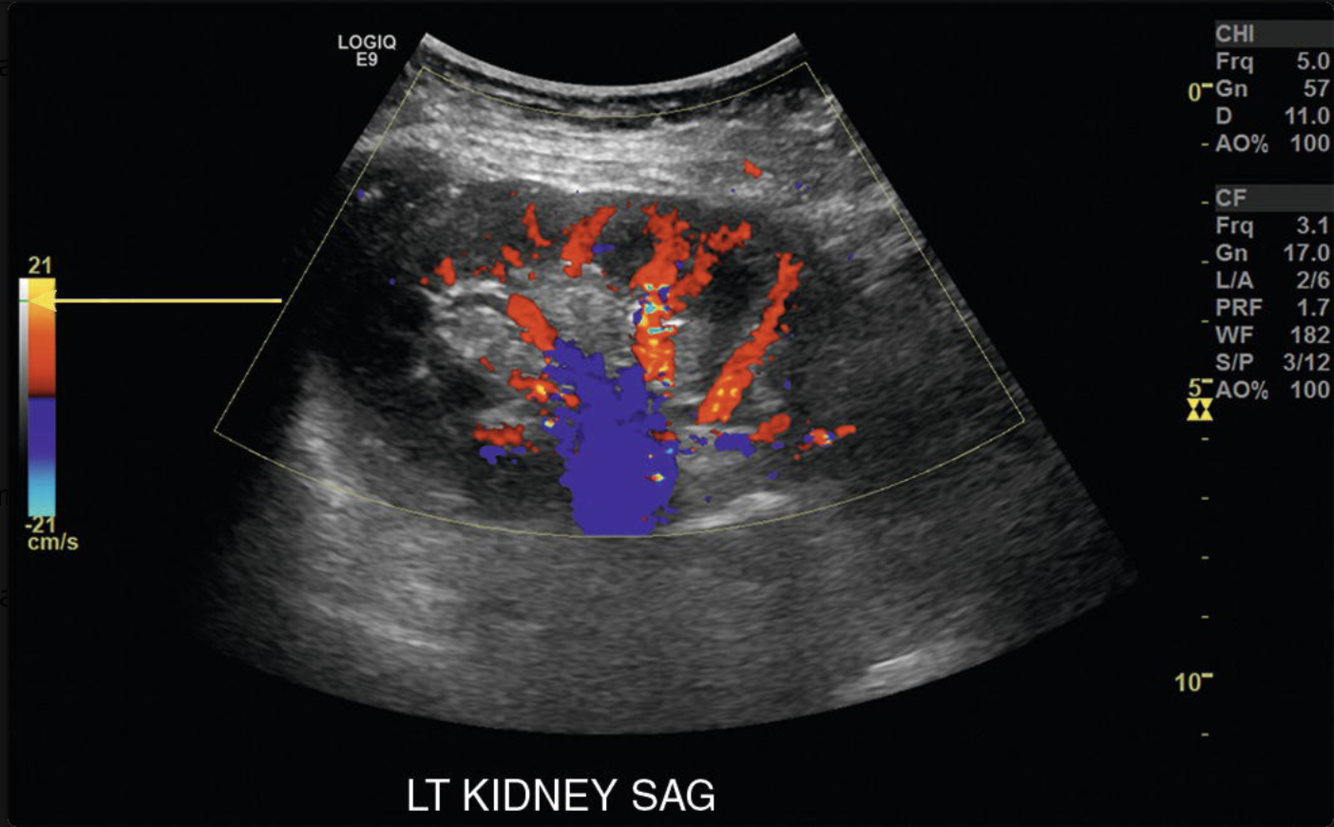

Power Doppler: